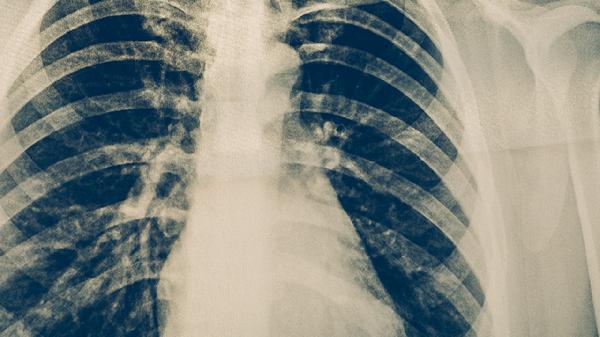

肺癌患者应定期复查胸部CT等影像学检查,遵医嘱使用吉非替尼片、注射用培美曲塞二钠等靶向或化疗药物。日常需保证优质蛋白摄入,适当进行呼吸功能锻炼,避免接触油烟等刺激性气体,保持居住环境通风良好。出现咯血、持续胸痛等症状需及时就诊。